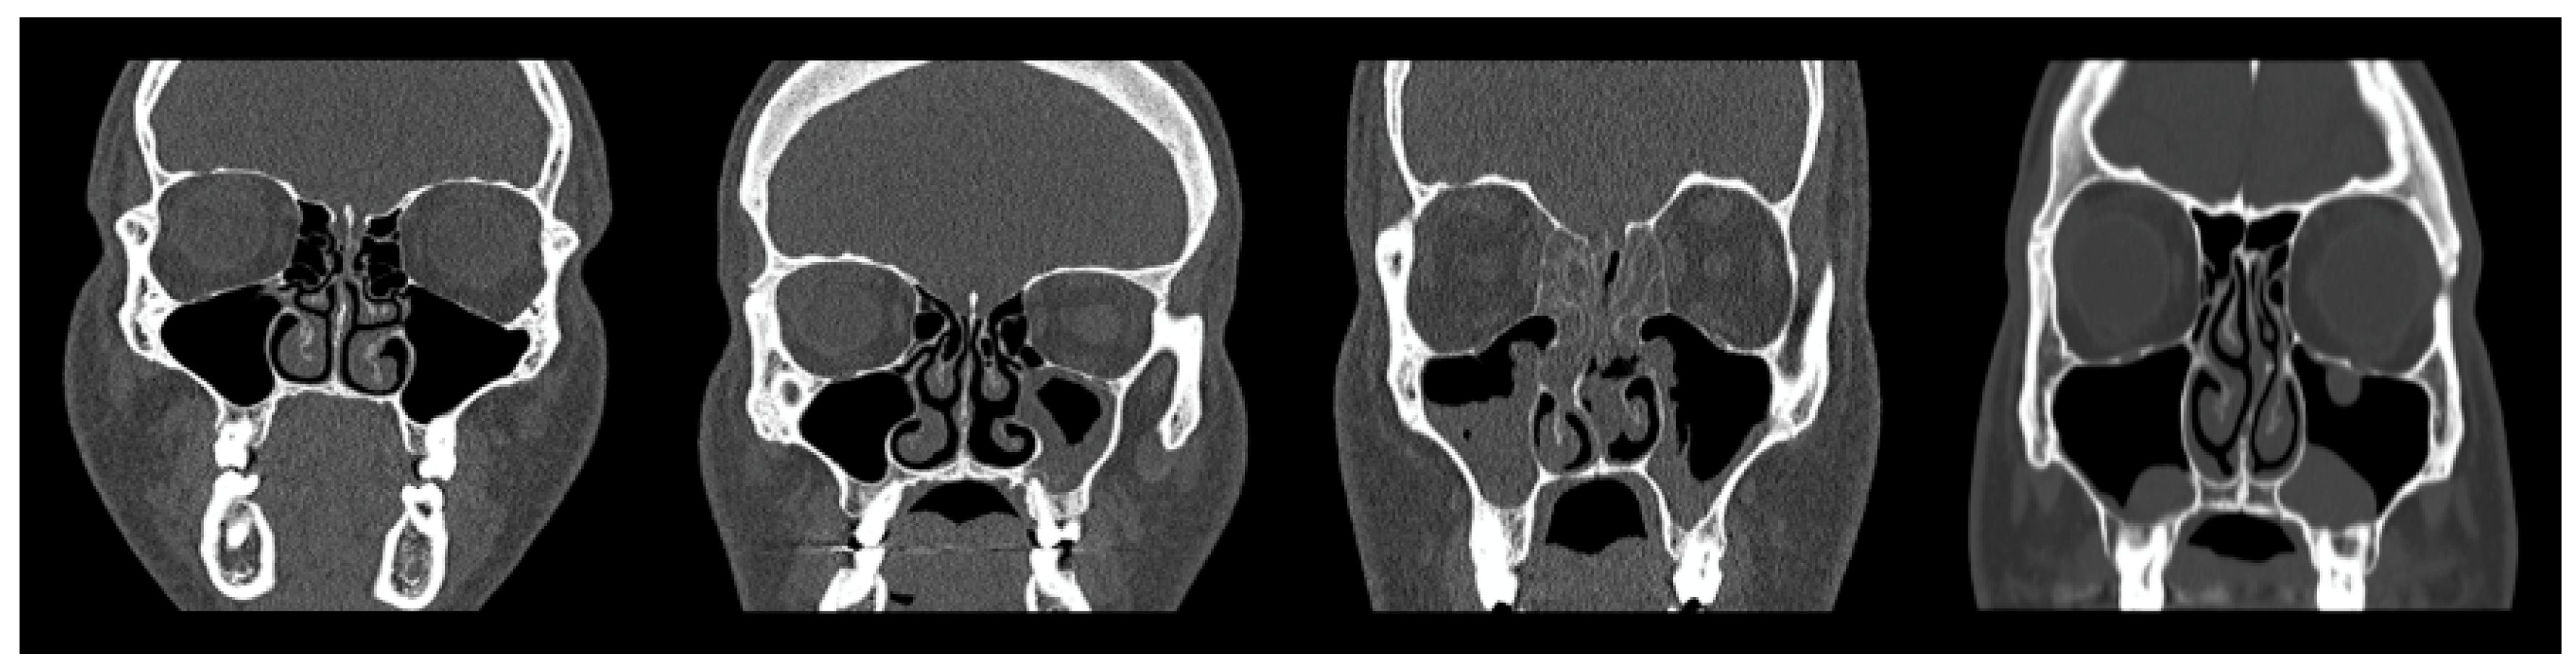

Following quality control, two experienced radiologists were engaged to manually evaluate and label the maxillary sinus findings into four distinct classes: Normal Maxillary Sinus (Normal MS), Opacified Maxillary Sinus (Opacified MS), Polyposis, and Retention Cysts. A visual illustration of the classification is presented in Figure 3, The first column (form left) column shows a normal sinus, the second column depicts partial opacification (Opacified MS), and the third and fourth columns represent Polyposis and Retention Cysts, respectively.

Recognizing that visual interpretation of CT images can be subjective, and different radiologists may interpret images differently based on their experience, interobserver variability was expected. To formally measure the level of agreement, Cohen’s Kappa [38] was employed, resulting in a substantial agreement (k = 0.821). Based on mutual consensus, the collected images were reliably categorized into the four predefined classes.

Figure 3. CT samples illustrating representative cases from each diagnostic category.